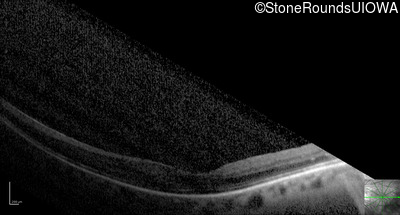

Optical Coherence Tomography - Right - 20/100 +1

Exemplar / OCT Stack

OCT Stack